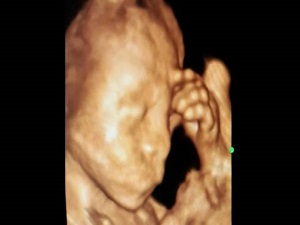

Anne karnında düşünen çocuk